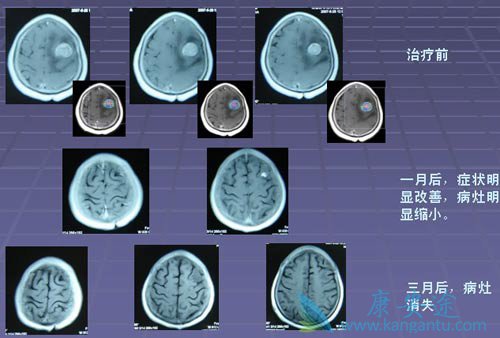

在大多数人的意识里,癌症就代表着绝望与死亡。但据中国工程院院士、中国医学科学院肿瘤医院孙燕教授2011年介绍:“肿瘤科医生患癌后, 80%都得到了治愈(5年生存)特别是一些发生肺癌脑转移,目前依然带瘤生存。”。而国家癌症中心全国肿瘤防治研究办公室随访至2010年年底的数据分析显示:我国全部癌症5年生存率为30.9%。

徐林友本身是肺癌医生,2011年1月自己却被查出肺癌脑转移,当时被医生判定为“很难活过100天”,如今6年过去了,仍旧活得很健康。所谓五年生存率,对于一个癌症病人来说,从临床标准来看,可以说是临床治愈了!